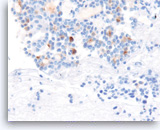

Undifferentiated anaplastic carcinoma,

Pancreas FNA, Cell Block.

The tumor cells are strongly positive for vimentin. The finding raises the possibility of a sarcoma or melanoma, but does not exclude the possibility of a carcinoma.

40X

Undifferentiated anaplastic carcinoma,

Pancreas FNA, Cell Block.

The tumor cells are strongly positive for vimentin. The finding raises the possibility of a sarcoma or melanoma, but does not exclude the possibility of a carcinoma.

40X